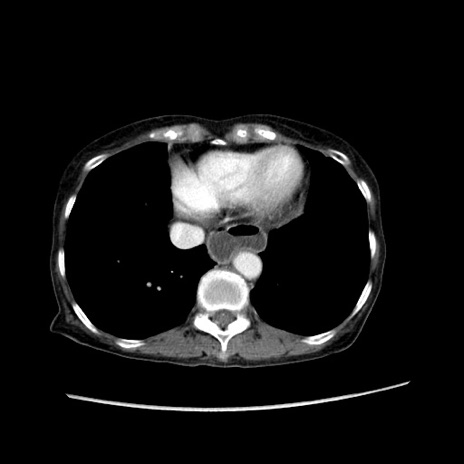

症例25(横断像)

【症例】80歳代女性

【主訴】胸のつかえ感

【現病歴】約9時間前に食後から胸のつかえた感じあり、嘔吐あり、来院。

【既往歴】胃癌(全摘)、胆摘、虫垂炎

【身体所見】心窩部に圧痛あり、反跳痛なし。

【データ】WBC 5700、CRP 0.05